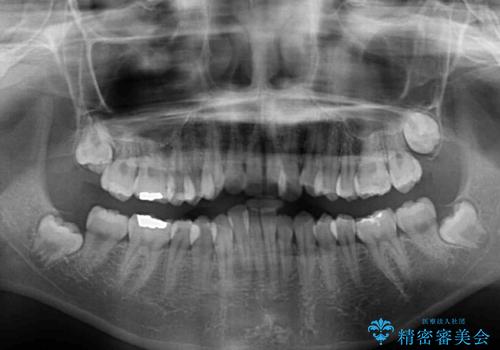

- 上下のデコボコと前歯のクロスバイトを改善したいとのことで来院された患者様です。

極力短期間で治療したいとのことで、ワイヤー装置による矯正治療を行うこととしました。

- 症状により、抜歯が必要な場合があります